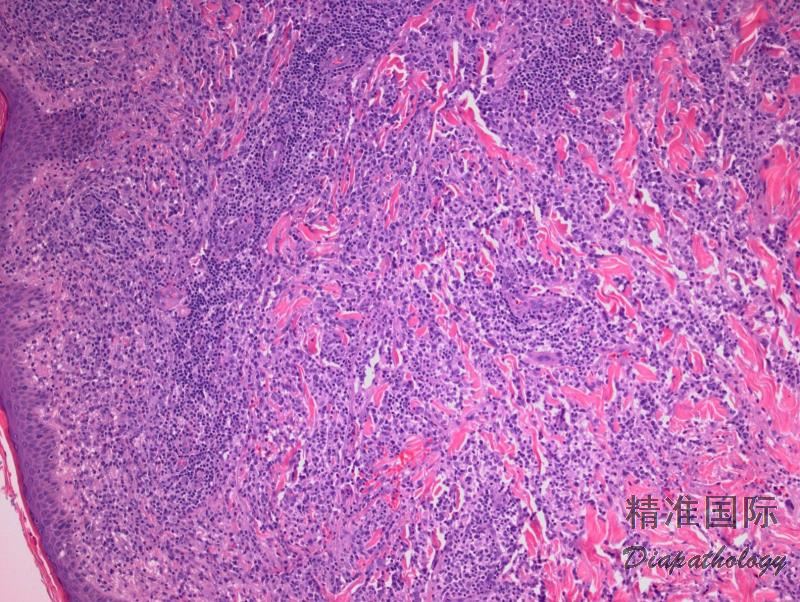

肿瘤细胞弥漫侵润伴组织地图样坏死,常累及血管(血管中心性生长),致管壁损伤、纤维素样坏死。散在凋亡小体、坏死细胞残影、核碎屑及纤维素性和血性渗出易见。